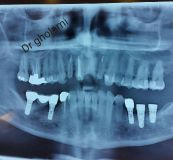

معرفی سیستم SPI همراه با جراحی زنده و Immediate Loading - آبان ۹۵

جراح وسخنران : استاد دکتر غلامعلی غلامی